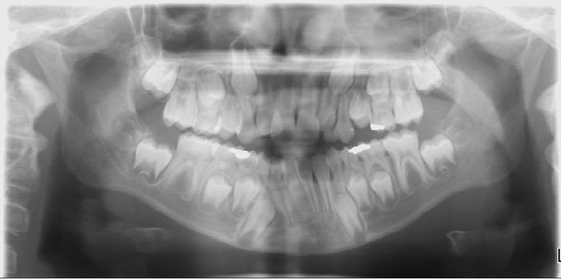

Digital x-rays

Digital radiography is a new X-Ray technology that eliminates the use of film and environmentally harmful chemicals. With digital x-rays you won't have to wait for an x-ray film to be developed. The image is immediately available on a computer monitor in your treatment room.

More importantly, digital radiography exposes you to up to 90 percent less radiation than traditional film x-rays. It's much safer than the old technology. The digital images can be enlarged and allows you to see what we do, helping us demonstrate and explain your treatment plan. This technology allows us to communicate with our specialists quicker by allowing us to emailing images instantaneously.